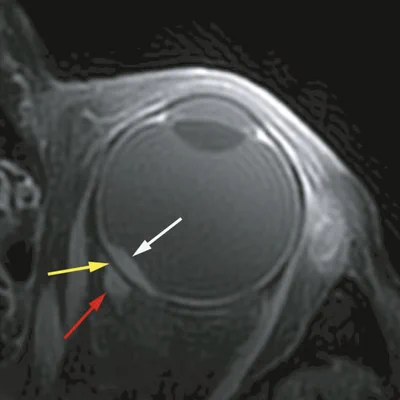

Until recently, MRI was scarcely used in care for patients with eye tumours. In the last years, we have been one of the pioneers in bringing ocular MRI to the clinic and proving its added value. Within our group we have developed high resolution scan protocols of the eye, which include a well-adjusted combination of dedicated hardware, such as an eye coil, and acquisition protocols that are robust against eye motion.

While we continue further tailoring these protocols for new applications, such as the eye lids, part of these technologies have been incorporated into clinical scanners. Together with our clinical partners, we have extensively studied the radiological characteristics of uveal melanoma, the most common primary eye tumour in the Netherlands. Currently, we are extending these analyses to other types of eye tumours, while we are also exploring its potential use as an early marker of therapy response and as a prognostic marker.